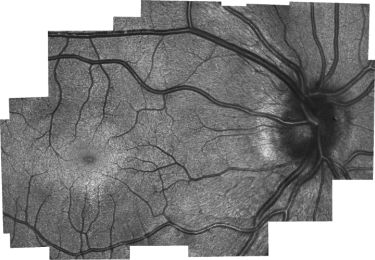

The new device was then given to clinicians for testing on adults, which proved that it was capable of getting accurate photoreceptor density information. It was also used for research imaging in children who were already having an eye exam under anesthesia.

"But because children have never been imaged with these systems before, there's no gold standard that we can compare it to," LaRocca explains. "The results do, however, match theories of how cones migrate as the eye matures. The tests also showed different microscopic pathological structures that are not normally possible to see with current lower-resolution, clinical-grade handheld systems."